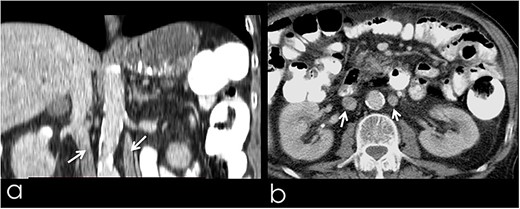

An 82-year-old Caucasian male was diagnosed with obstructive jaundice due to pancreatic duct adenocarcinoma. Computer tomography (CT) and magnetic resonance imaging (Figs 1 and 2) revealed a resectable tumor of the head of the pancreas, a duplicated IVC and a PV trifurcation. The two common iliac veins did not join together at lumbar 4 (L4) vertebra level but ascended separately along the celiac aorta, representing right and left IVC. Specifically, the right external and internal iliac veins joined, forming the right common iliac vein that ran along the abdominal aorta, representing the right IVC. The left IVC formed exactly like the right one while draining to the left renal vein (Fig. 1). This variation can be characterised as ‘type 2a’ in accordance with the classification shown in Fig. 3 (type 2a). Moreover, in our patient, a Whipple procedure was performed without post-operative complications.

(a) Coronal image from CT with contrast, presenting the duplicated IVC (arrows); (b) transverse image from CT with contrast, presenting the duplicated IVC (arrows).